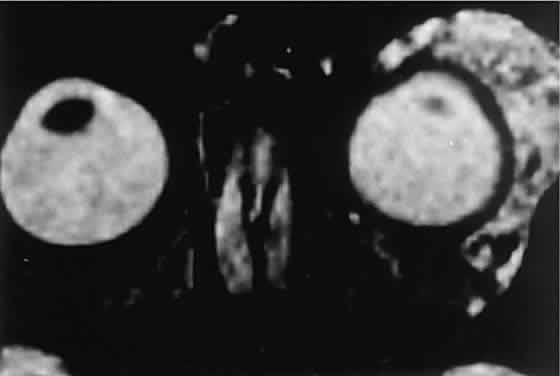

In dacryoadenitis, external inflammatory signs are localized to the superotemporal quadrant, and CT shows enlargement of the lacrimal gland (Fig. 24). Lacrimal gland inflammation may be bacterial, viral, or a variant of IIPT. It is possible, however, that many cases of “idiopathic” dacryoadenitis represent unidentified viral infections. In bacterial dacryoadenitis, a leukocytosis with a left shift may be present.96 In questionable cases, a 1-week course of oral antibiotics can be administered to these patients. Among children, the probability that an enlarged lacrimal gland represents neoplasia rather than inflammation is lower than among adults, although epithelial lacrimal gland tumors occasionally may occur in the pediatric population and can produce external inflammatory signs. If the general signs and symptoms of IIPT are lacking, a biopsy should be performed.

Fig. 24. A. Nonbacterial dacryoadenitis may be unilateral or bilateral. External inflammatory signs are maximal in the superotemporal quadrant. B. The left lacrimal gland is enlarged, with a shape molded by the globe and orbital walls. A neoplasm usually can be ruled out by analysis of the history, CT findings, and echographic characteristics, but a biopsy may be required in equivocal cases.